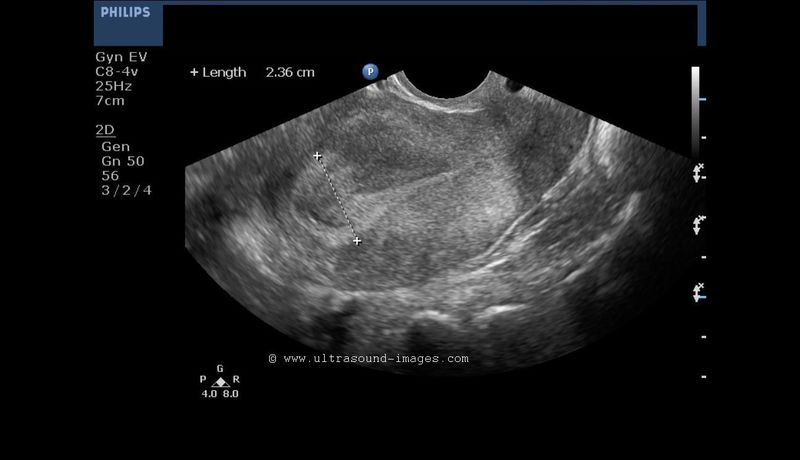

Hypoplastic uterus

Rudimentary uterus.

Transabdominal ultrasonography of the pelvis in this 33 yr. old female patient revealed a very small.

Transvaginal ultrasound images show the uterus measuring about 2.5 x 2 x 1 cms., clearly too small for a woman in the 30s. The uterine cavity (endometrial cavity shows minimal fluid within it). Transverse section ultrasound image shows markedly reduced intercornual distance (less than 2 cms.).

The rudimentary Fallopian tubes are visible, but the ovaries appear very small. Clearly this lady appears to have a hypoplastic uterus with very small ovaries. The chances of conception in such a woman are very low or unlikely.